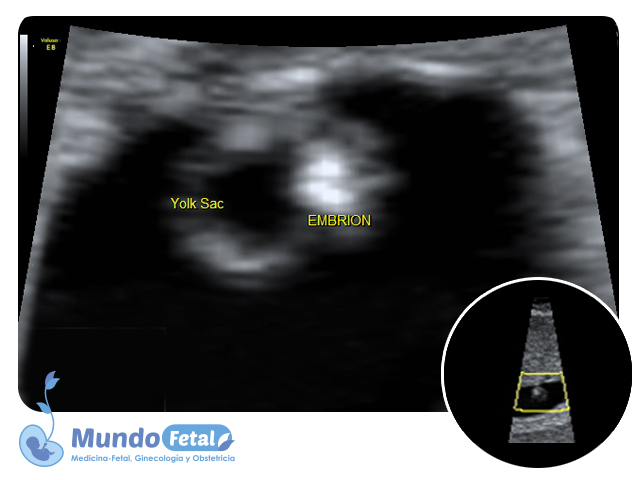

Ultrasonido Temprano 1er Trimestre (Menor 11 Semanas)

Estudio que nos permite la confirmación del embarazo, numero de bebes, valoración de líquido amniótico, placenta, vitalidad por medio de la frecuencia cardiaca, crecimiento armónico y edad gestacional estimada, descartando alguna complicación propia de esta edad.